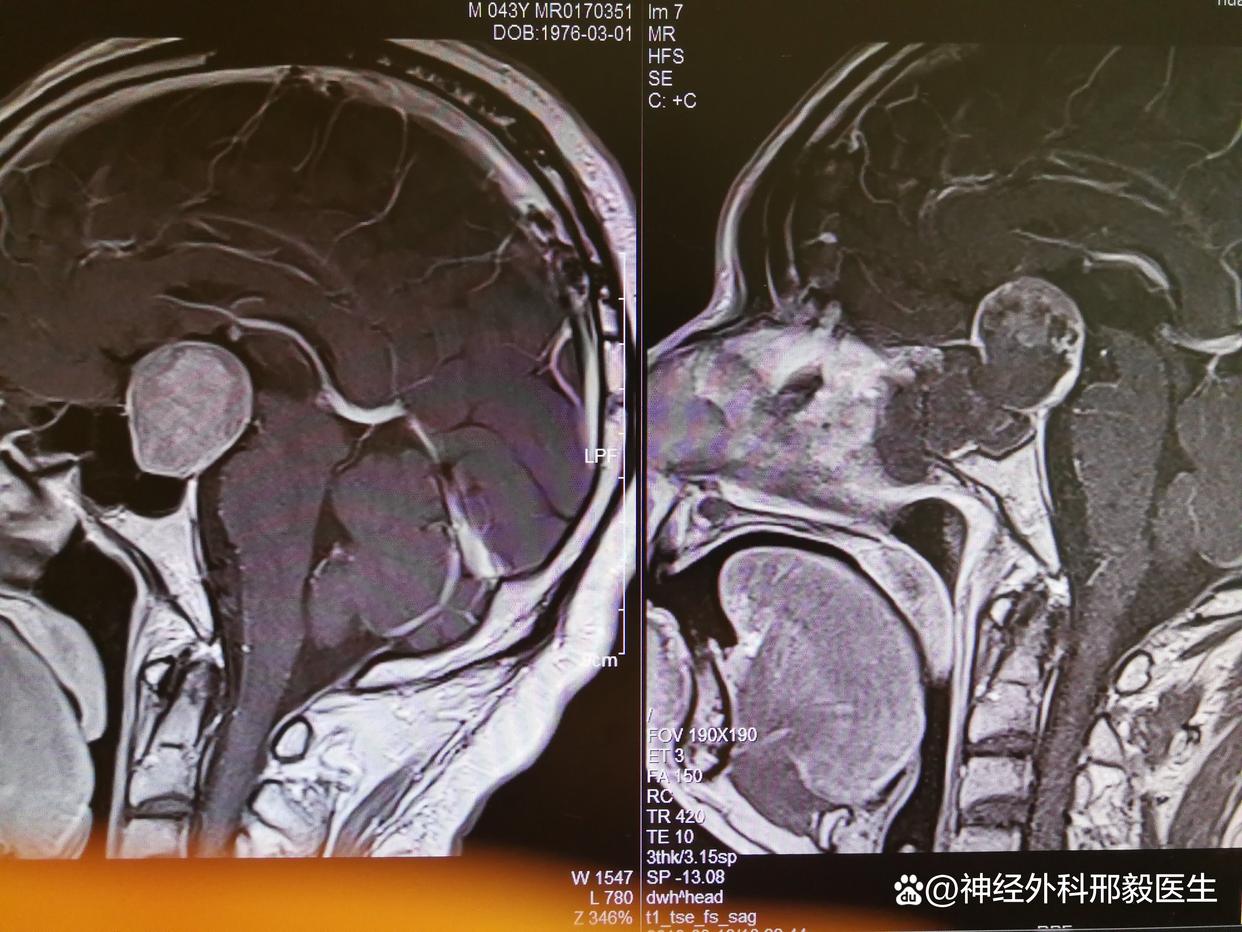

垂体瘤引起的视力下降,手术后视力还能恢复吗?

首先,垂体瘤是一种比较常见的良性肿瘤,它可以引起许多症状,其中之一就是视力下降。当垂体瘤压迫到视神经时,就会导致视力下降。这时候患者可能会出现视物模糊、视力减退、视野缺损等症状。如果肿瘤继续增大,还可能导致失明。

那么,垂体瘤引起的视力下降在手术后是否可以恢复呢?一般来说,如果垂体瘤手术能够完整地切除肿瘤,解除对视神经的压迫,那么视力是可以得到恢复的。但是,手术对视神经可能会造成一定的损伤,因此术后视力恢复的情况会因人而异。

在手术前,医生会对患者进行全面的检查和评估,包括视力、视野、眼底等方面的检查。这些检查结果可以帮助医生了解患者的病情和制定最佳的手术方案。同时,医生也会告知患者手术可能存在的风险和并发症,以及术后视力恢复的情况。